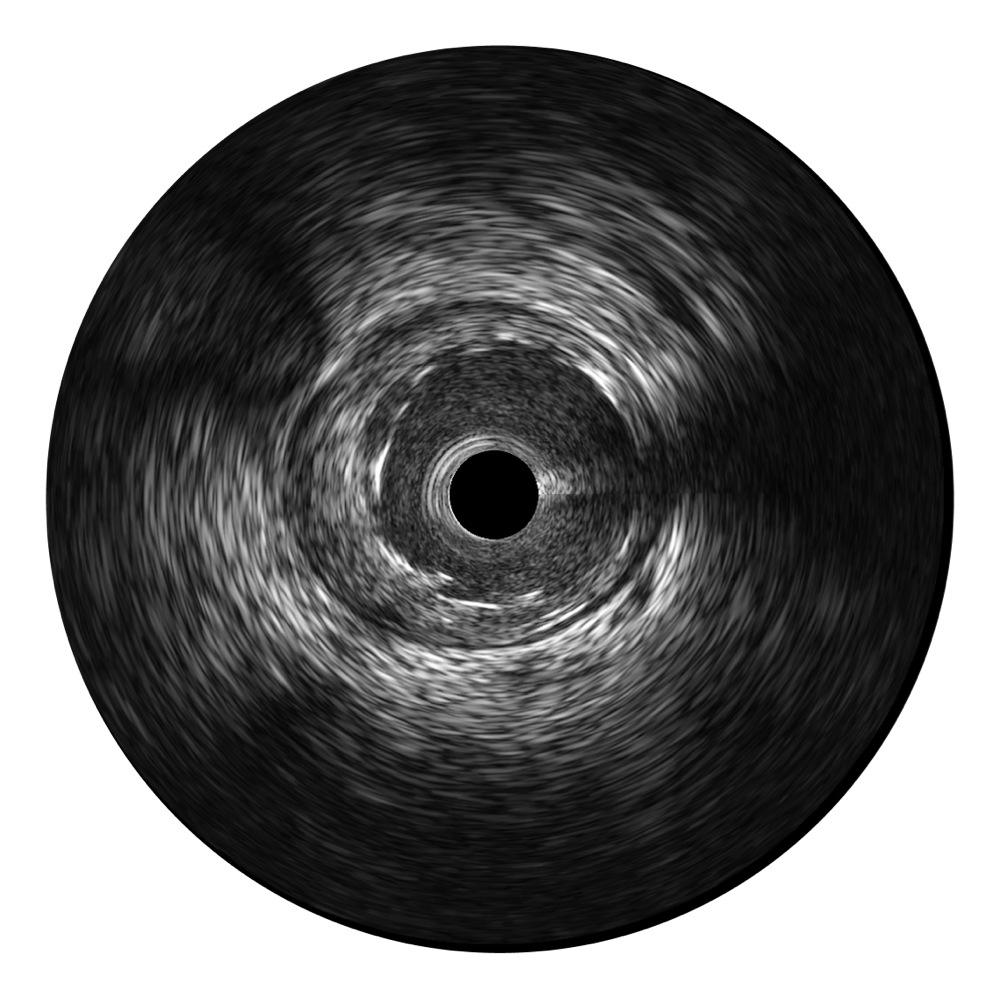

DB中国旗舰官方网站宽频IVUS图像

传统IVUS图像

对比传统IVUS导管成像,DB中国旗舰官方网站宽频IVUS图像的近场支架梁显影更细腻,远场中膜外血管仍清晰可辨,兼顾远中近,兼顾分辨力与穿透深度